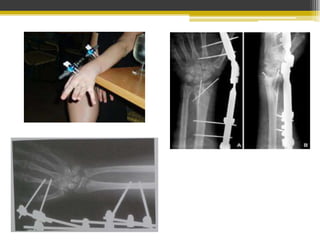

En pacientes con poco desplazamiento o mínima conminución

En Fx conminutas, desplazadas o abiertas no subsidarias de

reducción cerrada ni fijación interna.

Usada en Fx con desplazamiento articular

Yeso postoperatorio según estabilidad